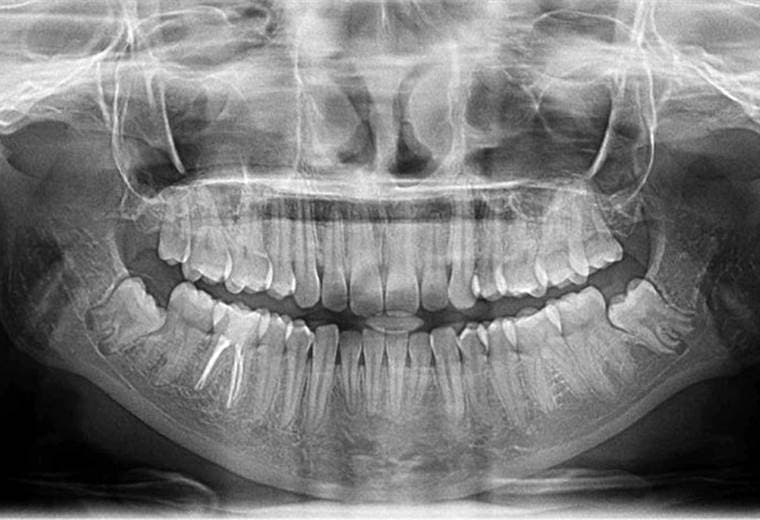

¿Cuándo se deben extraer las cordales o muelas del juicio?

No a todas las personas les salen las famosas cordales o muelas del juicio, pero en caso de que sí, surgen muchas preguntas como por ejemplo si será necesario extraerlas.